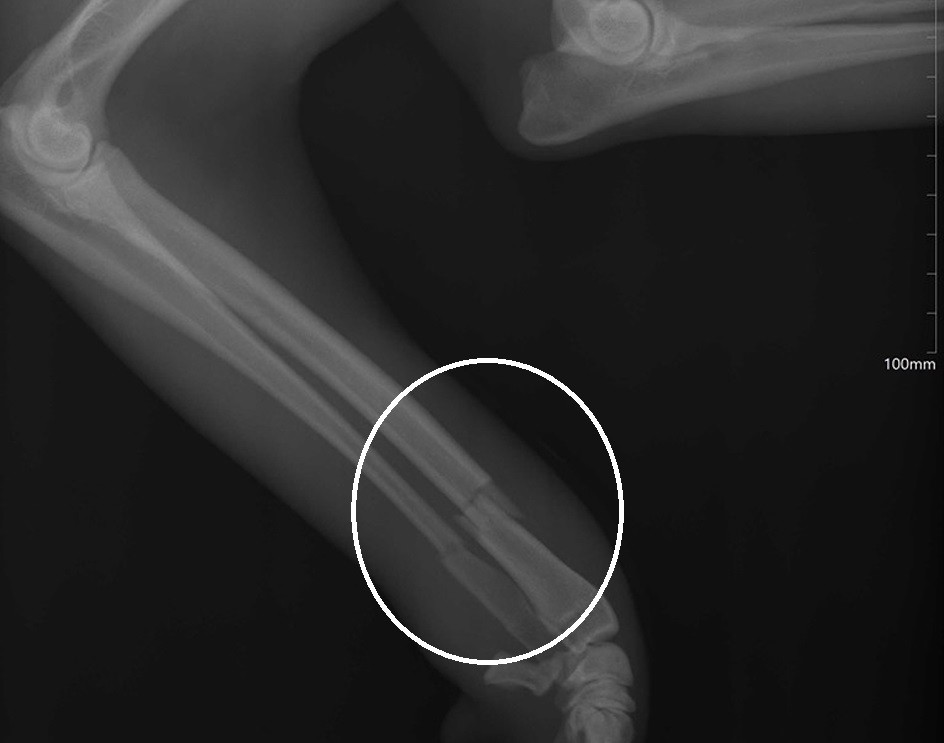

Mivel nyári időszakban gyakori a házi kedvencekkel való kirándulás, valamint hosszabbak a napok, és emiatt tevékenyebbek az állatok, gyakrabban fordulnak elő különböző balesetek (járműgázolás, állatok közötti verekedés, macskáknál a kerítésre való fennakadás, de olyan esettel is találkozni, amikor emeleti lakásból légy vagy veréb után kapva esett vagy ugrott ki az állat). Nemrég egy hatodik emeleti lakásból kipottyant kilenc hónapos macska szorult kezelésre, egyéves kutya alkarját is rögzíteni kellett, egy két hónapos Bichonnak pedig mind a négy kéztőcsontja eltörött, egy kiskorúval játszva/birkózva. Amint a szakember elmondta, hasonló esetekben a végtagok rögzítésére sínt használnak, és naponta újrakötözik. Mivel a két hónapos kutyus fiatal, viszonylag hamar, két hét alatt gyógyul, kicsit bogos, de használható végtagjai lesznek. A felsorolt esetek egyértelmű velejárója a fájdalom.

Kilenc hónapos macska törött végtagja, hatodik emeleti lakásból esett ki